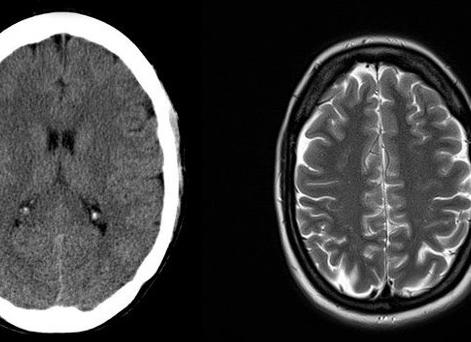

Рентгеновская компьютерная и магнитно-резонансная томография используются при диагностировании опухолей головного мозга. При КТ идет послойное исследование органов и тканей с помощью рентгеновского облучения, затем проводится компьютерная обработка результатов.

Магнитно-резонансная томография основана на использовании электромагнитных волн на фоне мощного магнитного поля, исследование также идет послойно. Самые высокие результаты – при диагностировании позвоночника и сердца.

МРТ лучше «видит» мягкие ткани (мышцы, мозг, нервы, межпозвонковые диски, сосуды), но совсем не «видит» кальций, находящийся в костях. А КТ напротив лучше «видит» костную ткань.

С помощью МРТ-исследования хорошо «просматриваются»мягкие ткани: мозг, мышцы, нервы, связки, межпозвоночные диски и т.д. Но, плохо «видны» твердые ткани — кости скелета, содержащие кальций. Здесь используется компьютерная томография или рентгенография .

Следовательно, МРТ-исследование предпочтительно при поражении мягких тканей. Оно широко применяется в нейрохирургии и неврологии (хорошо просматриваются старые травмы головного мозга, инфаркты головного мозга в поздней стадии развития, а также выявляются опухоли головного и спинного мозга). Можно изучить состояние сосудов головы и шеи, используя естественное кровообращение как контраст.

Магнитно-резонансная томография малоинформативна при болезнях легких, желчного пузыря, переломах костей.

Компьютерная томография идеальна для диагностики повреждений костей, травм почек, легких. КТ-исследование информативно для диагностики свежих кровотечений, поэтому применяется при свежих травмах головы, груди, живота, инфарктов головного мозга на ранней стадии.

При магнитно-резонансной томографии хорошо визуализируются мягкие ткани: мышцы, связки, хрящи, сосуды, нервы, головной и спинной мозг и др. Поэтому данный метод исследования показан при подозрении на разрывы связок, грыжи межпозвонковых дисков,  травмы и опухоли головного и спинного мозга, инсульты (в поздней стадии).

Костные структуры на МР-томограммах видны хуже. Для более детального исследования костей рекомендовано выполнять РКТ или рентгенографию.  Кроме того, на КТ хорошо видно свежее кровоизлияние, поэтому данный метод используют при обследованиях больных с инсультами в ранней стадии, с повреждениями головы, грудной клетки и брюшной полости.